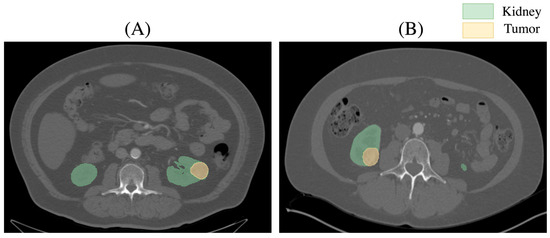

The Kidney Tumor Segmentation-2019 dataset is a widely used benchmark for developing and evaluating algorithms in medical image analysis. It consists of annotated Computed Tomography (CT) scans of patients with kidney tumors, providing ground truth segmentations for three classes: background, kidney, and tumor. This dataset is designed to facilitate research on automated segmentation methods, with the goal of improving the accuracy of detecting and delineating renal masses. The KiTS dataset poses significant challenges due to variations in tumor size, shape, and location. Figure 2 shows axial CT slices from the KiTS dataset with segmented kidneys (green) and tumors.

Figure 2. Representative axial CT slice from the KiTS dataset depicting a renal tumor and surrounding kidney anatomy. The tumor is located at the lower pole of the left kidney in (A) and at the lower pole of the right kidney in (B).